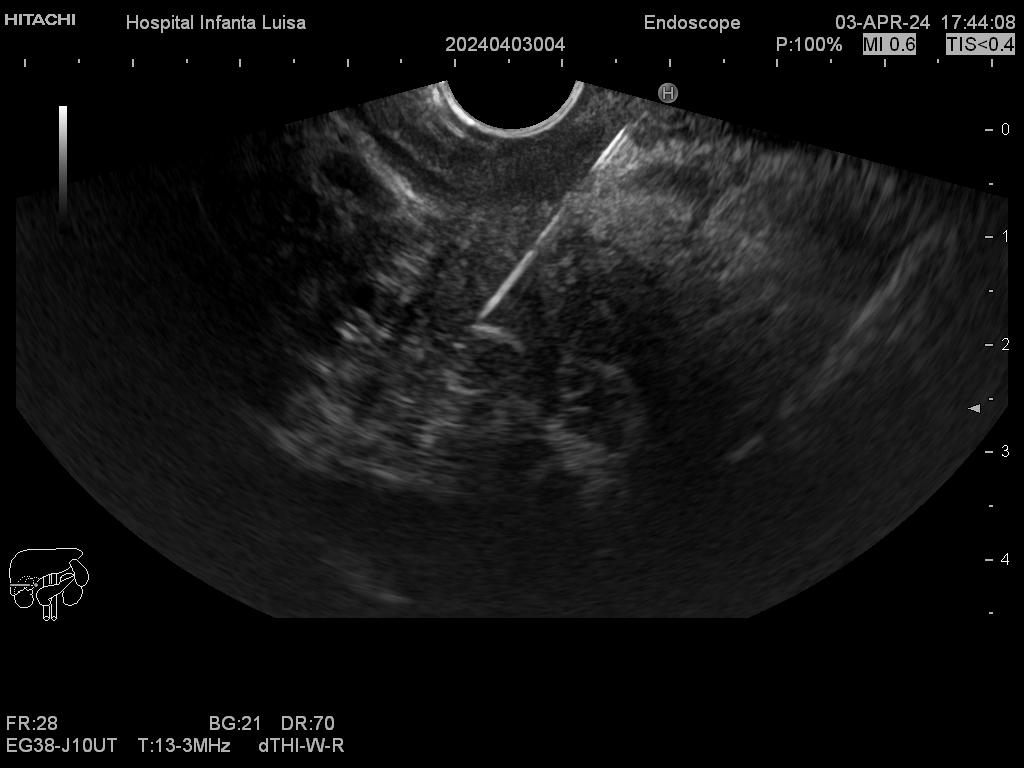

Igualmente, es una técnica básica hoy día en el estudio de todo tipo de lesiones pancreáticas, en la determinación de formaciones subepiteliales esofágicas, gástricas (más frecuentes) o duodenales, o en el estadiaje de patología tumoral a estos niveles. La Ecoendoscopia permite la toma de biopsias a estos niveles, con control endoscópico y ecográfico, siendo una técnica de gran rentabilidad diagnóstica y seguridad.